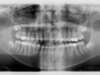

Panoramique